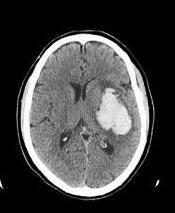

AVE hemorrágico intraparenquimatoso

O que mostra a TC?

Lesão hiperdensa (branca) com edema ao redor (halo hipodenso - cinza), logo no início dos sintomas.